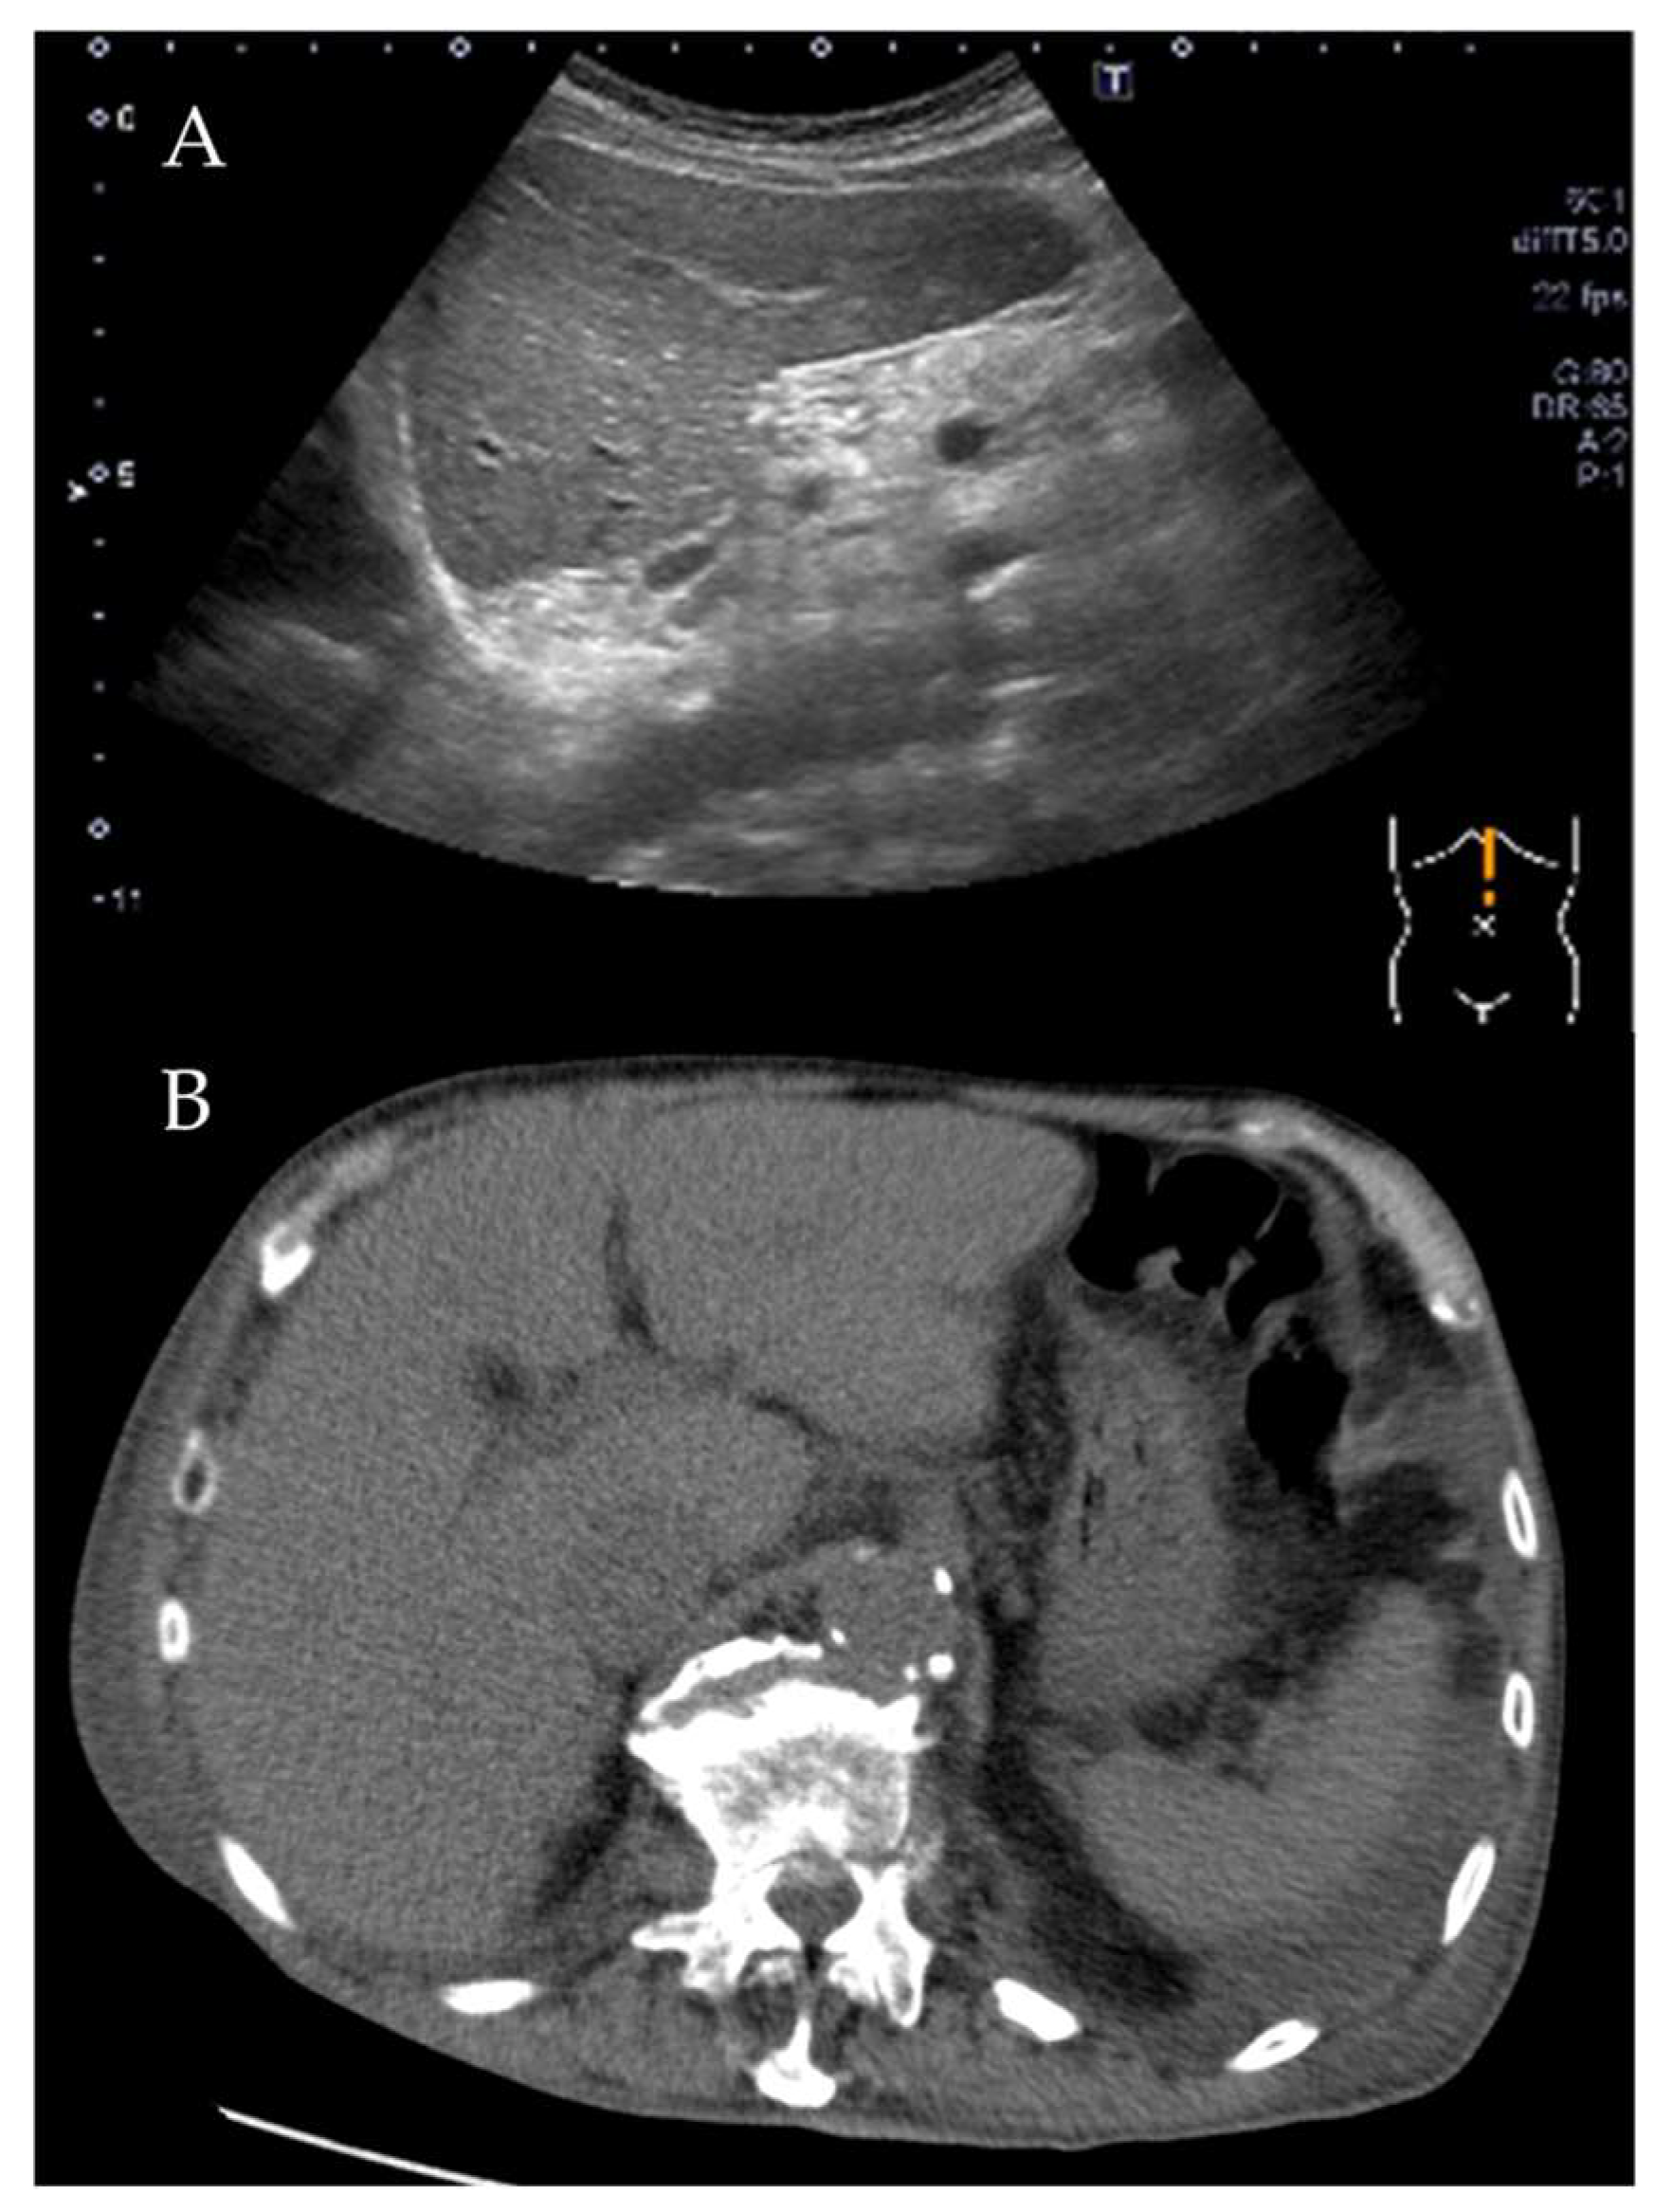

2. Case Presentation